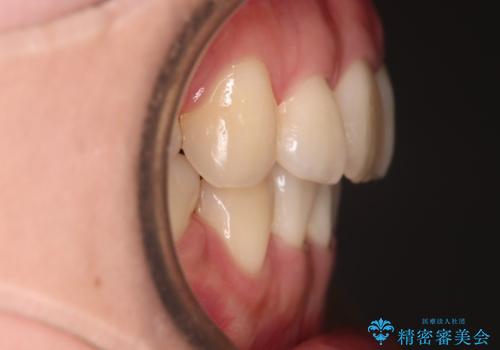

【審美装置】前歯のデコボコを綺麗に

- 上の前歯のデコボコが気になるということで来院されました。

叢生量(デコボコ)が多いため、上下左右4番目の歯を抜歯してワイヤー矯正を行う治療計画を立てました。

主訴である前歯のデコボコが改善され、噛みあわせも綺麗になりました。

歯肉退縮もなく、予定通りに治療を終えることができ良かったです。